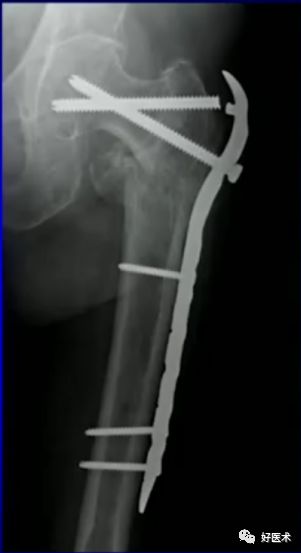

DCS入点高因而可于骨折近端增加了数枚螺钉固定,増加了近端的抗屈曲旋转能力,达到牢固固定,从而一定程度上降低术后并发症发生率,补充了DHS对粉碎性骨折的不足。

由于DHS不足,出现了大转子稳定接骨板

-

扩大DHS临床指征

防止大转子外移

防止股骨干内移

稳定大转子骨块

并未从根本上解决生物力学问题。

以髓内固定为主:

髓内固定成为首选趋势

更多骨科医生倾向于选择髓内钉治疗转子间骨折。